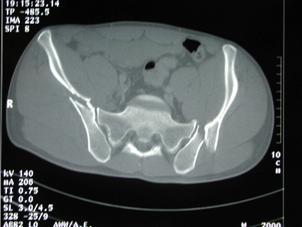

TRAUMATISMELE PELVIENE

Traumatism

pelvian Hemipelviectomie dreapta posttraumatica

Fractura Malgaigne Fractura Malgaigne. Imagine CT

Compresie laterala

Fracturi pelviene multiple Fracturi pelviene multiple

Compresie bilaterala Compresie bilateralaAspect CT